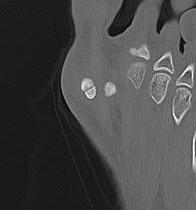

CT demonstrates irregular borders consistent with fracture of tibial sesamoid